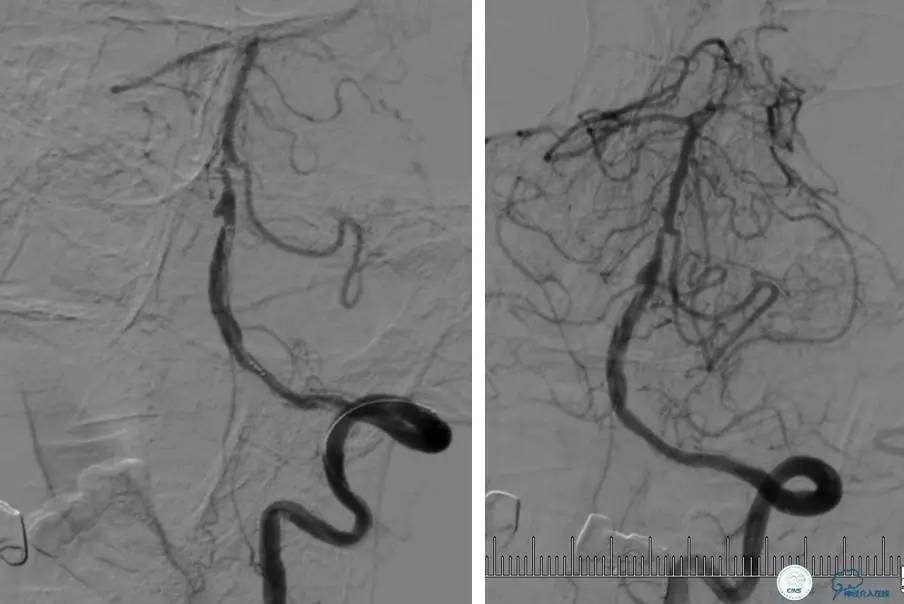

患者:58岁男性,反复头晕、肢体无力3月,当地造影见多发颅内动脉狭窄、闭塞,转来我院。

▼首先行颈动脉CTO开通术,手术顺利,Wallstent支架。

▼1周后行右侧椎动脉V4段CTO开通术。

▼微导丝穿过狭窄段,微导管造影,小球囊预扩张,2mm。

▼根据血管情况选择较大球囊再次预扩张。

▼置入2枚Wingspan支架,手术成功。

▼术后即刻CT,梗死灶内再灌注出血。

患者无症状,中性治疗。4月21日电话随访,一般情况好,当地CT示出血吸收期。